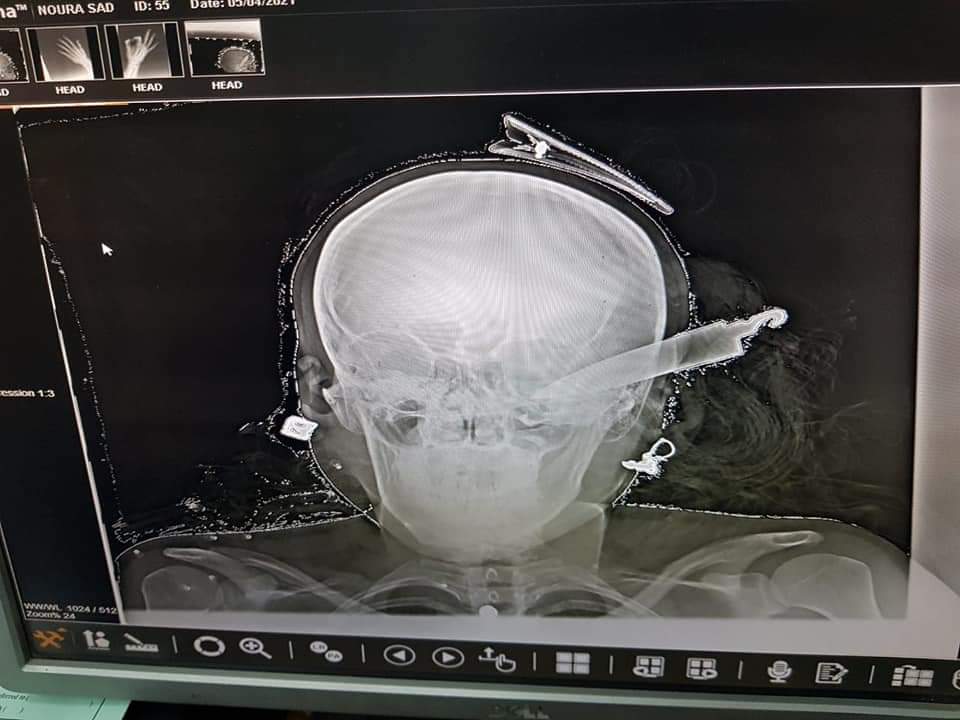

تمكن الفريق الطبي بمستشفى "شبين الكوم" التعليمي بمحافظة المنوفية، اليوم الثلاثاء، من إنقاذ حياة سيدة تعرضت لضربة بسلاح أبيض "سكين" في رأسها.

ونجح الفريق الطبي، برئاسة الدكتور إسلام العربي، وإشراف الدكتور محمد موسى، من استخراج السكين، فيما لا تزال السيدة تحت الملاحظة بالعناية المركزة بالمستشفى.